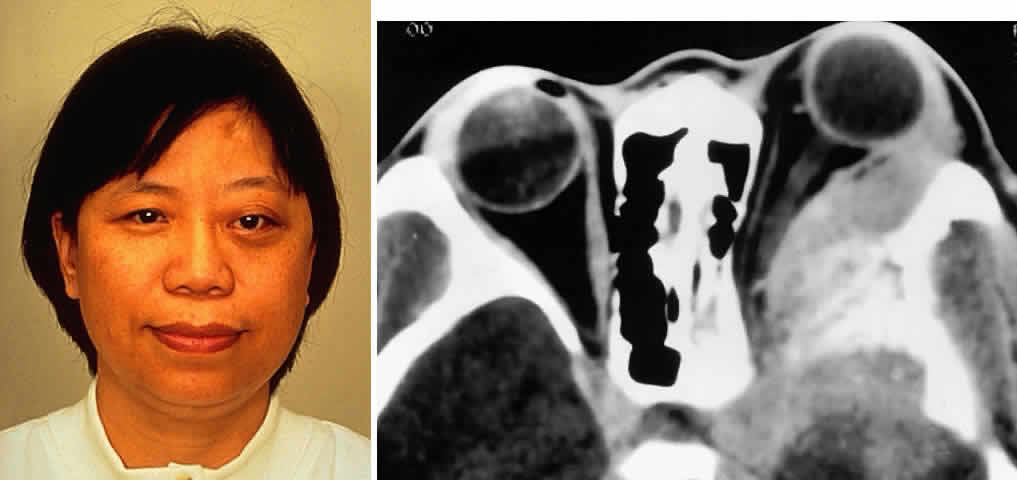

Meningiomas of the sphenoid wing are prone to extend into the orbit along the lateral wall as an en plaque component (Fig. 4). These desmoplastic, infiltrative lesions generally have some element of hyperostosis. The orbital and visual manifestations reflect the location of the mass, with the more medial tumors causing cranial nerve palsies, visual deficits, and venous obstructive signs and symptoms (e.g., edema, chemosis). More remote tumors are manifested by raised intracranial pressure or mass effect. Tumors of the greater wing of the sphenoid are evidenced by fullness of the temporalis fossa and proptosis, with intracranial symptoms occurring as a late symptom (Fig. 5). Olfactory groove meningiomas present with lost sense of smell, personality changes, papilledema, or apical orbital infiltration or compression.

Fig. 5. A 48-year-old Chinese woman had undergone previous frontotemporal craniotomy and partial excision of a left sphenoid wing meningioma. She presented 6 years later with progressive proptosis, visual loss, and numbness of the left cheek and upper teeth that developed during the preceding 2 years. On external examination, she had fullness of the temporalis fossa, an axial proptosis of 11 mm, and downward displacement of the left globe 2 mm (A). Ocular ductions were moderately restricted in all fields of gaze. She had no light perception, marked optic disc pallor, and an optociliary shunt vessel. CT scan revealed an extensive regrowth of meningioma involving the sphenoid wing, with soft tissue components in the temporalis and middle cranial fossae, parasellar region, and orbit, shown here on axial view (B). The lesion also involved the cavernous sinus and pterygopalatine fossa. She underwent a combined resection via the frontotemporal orbitozygomatic approach, followed by radiotherapy (50 Gy in 25 fractions over 5 weeks) for residual components in the cavernous and sphenoid sinuses. Two years after surgery, she remains comfortable and without radiographic evidence of tumor regrowth. Proptosis was reduced to 1 mm axially.